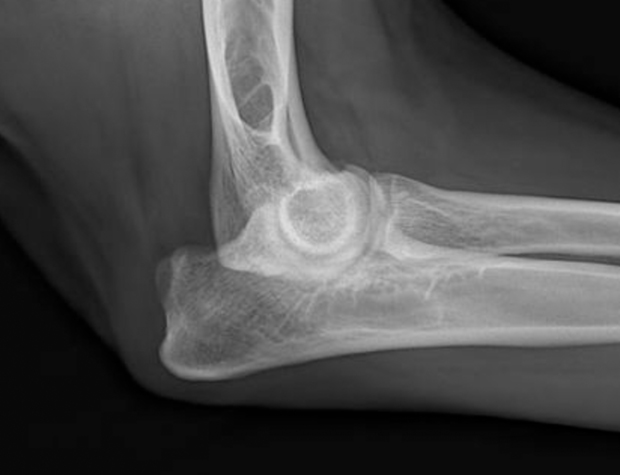

The elbow is known as the cubital joint and is created by the humerus, radius and ulna coming together in one joint. These three bones make the elbow somewhat different from the shoulder, hip and knee joints, in which only two bones are coming together to form a joint.

Normal elbow, radiograph.